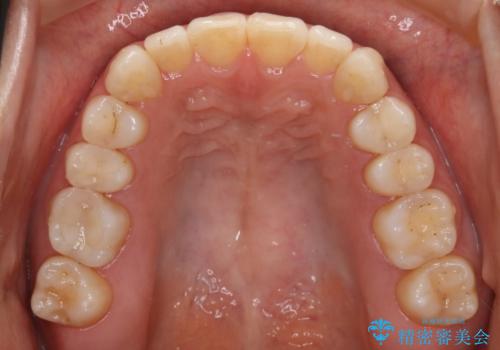

上顎の真ん中の歯の角度が、内側に傾いており、またその隣の歯が、唇側にずれてしまっていました。

上顎の前歯の傾きを改善することで、がたつきを治すためのスペースを確保しました。

また、それだけではがたつきを改善するスペースが不足していたため、歯の側面を削りがたつきを改善しました。